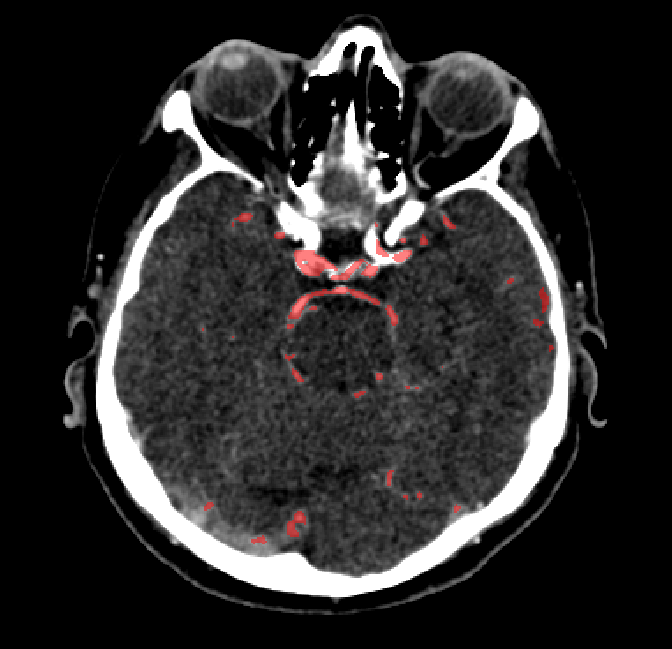

After fine-tuning, the two pre-train conditions appear to have little or no difference in terms of qualitative performance at the vessel segmentation task. However, when compared to the models trained only on real data, there are noticeable differences. Throughout Figures 4.3-4.9, the model pre-trained on scans with original CT noise is to be taken as representative of segmentation performed by the Perlin noise pre-training condition. Images showing the hand-labeled ground truth, as well as the unlabeled slice, are presented for comparison.

Figure 4.3: Segmentation on internal carotid arteries. Unaltered image (left). No pretrain model (mid-left). Fine-tuned model (mid-right). Hand-labeled ground truth (right).

Figure 4.4: Segmentations on regions near internal carotid arteries. Unaltered image (left). No pretrain model (mid-left). Fine-tuned model (mid-right). Hand-labeled ground truth (right).

Figure 4.5: Segmentations on a central slice. Unaltered image (left). No pretrain model (mid-left). Fine-tuned model (mid-right). Hand-labeled ground truth (right).

Figure 4.6: Segmentations on a central slice. Unaltered image (left). No pretrain model (mid-left). Fine-tuned model (mid-right). Hand-labeled ground truth (right).

Figure 4.7: Segmentations on regions near the top of the skull. Unaltered image (left). No pretrain model (mid-left). Fine-tuned model (mid-right). Hand-labeled ground truth (right).

Figure 4.8: Side view of segmentations on regions near the left side of the skull. Unaltered image (left). No pretrain model (mid-left). Fine-tuned model (mid-right). Hand-labeled ground truth (right).

Figure 4.9: Side view of segmentations. Unaltered image (left). No pretrain model (mid-left). Fine-tuned model (mid-right). Hand-labeled ground truth (right).

For vessels in the center of the head, all model types appear to accurately segment vessels. In certain cases, the models appear to learn to correctly avoid segmenting pieces of bone that could, in terms of shape and contrast, easily be confused with large vessels. An example of this can be seen in the frontal section of Figure 4.6.

The models appear to have a hard time segmenting vessels close to the skull surface. The model trained exclusively on patient data appears to struggle far more for these types on conditions than the fine-tuned models. Figure 4.8 shows an example of the fine-tuneds model having close to no trouble segmenting vessels near the left side of the skull, while the baseline model suffers heavily from false negatives. To lesser degree, this effect can also be observed in the frontal lobe of Figure 4.9 In the other hand, Figure 4.7 presents an example of both models failing to segment vessels near the top of the skull.

In the other hand, it should be noted that fine-tuned models suffered from false positives more often than models with no pre-training. The fine-tuned models appeared to occasionally segment regions near the skull, which although similar in intensity to vessels, had no resemblance in terms of shape. Examples of this are seen in Figure 4.4 near the occipital bone and near the right temporal bone. Examples of oversegmentation were observed to happen commonly around the internal carotid arteries. This is likely due to the amount of contact surface between the artery and the surrounding bone. There was also a tendency for all model conditions to segment bone regions that were similar in shape to large vessels (Figures 4.3 and 4.4). Bone structures in such regions have similar pixel intensities to the arteries transporting contrast material, which could explain the source of confusion for a model.

To our surprise, the models were able to occasionlly segment the shape of the internal carotid arteries correctly despite no boundary being visible to the naked eye between the vessel wall and the surrounding bone structure. An example of this can be seen in the fine-tuned model in Figure 4.3.